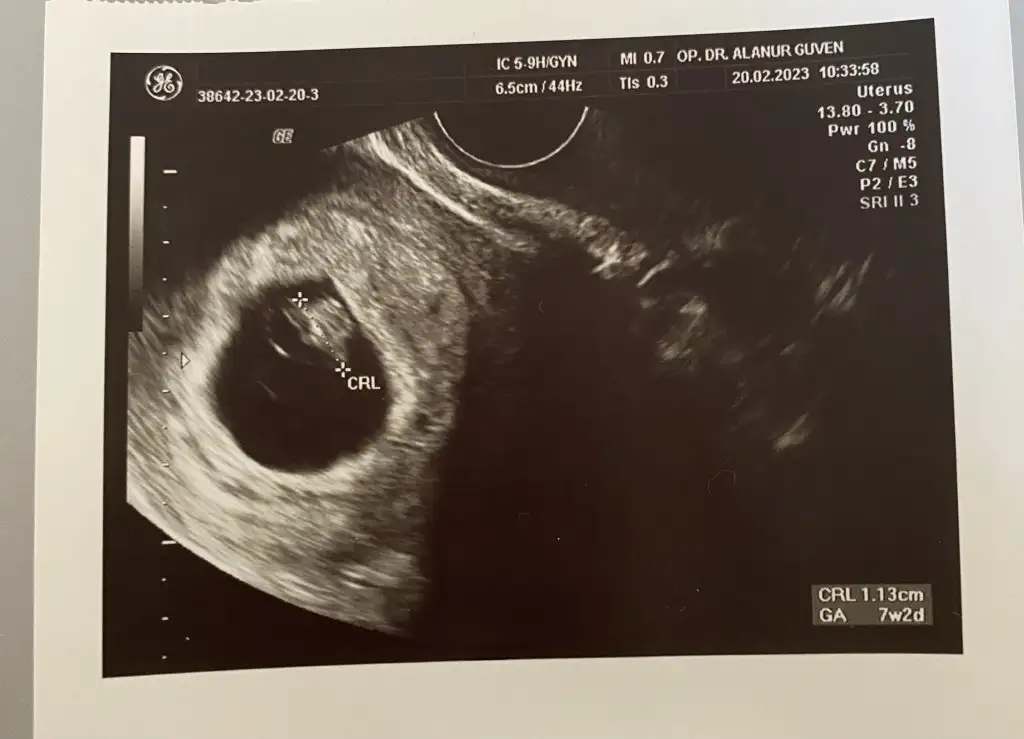

• 16793857404897884354304871002078.webp

16793857404897884354304871002078.webp

19,3 KB · Görüntüleme: 51